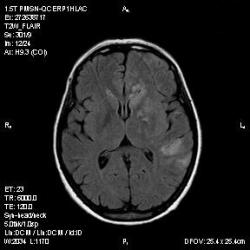

Из анамнеза - Женщина 45 лет. За год похудела на 15 кг (со слов матери), в последние месяцы случались эпизоды потери сознания. Онкозаболеваний и прочая в анамнезе нет. Сознание спутанное, из особенностей в анализах только подъем амилазы крови.

И это точно не РС, т.к. характер очагов другой, ни один из них не копит контраст, нет субтенториальных очагов (извиняюсь, я этого в сообщении не указал), нет клиники.

"Раскрою" карты. Мы подумали о синдроме MELAS (mitochondrial encephalomyopathy, lactic acidosis and stroke) - дословно, митохондриальная энцефаломиелопатия, лактоацидоз и инсульт. В качестве дифференциальной диагностики можно было бы предположить вирусный энцефалит, но опять-таки, расположение очагов смущает - только с одной стороны и в абсолютно различных структурах.

В данном случае мы видим импульную последовательность FLAIR - режим с подавлением сигнала от воды, поэтому ликвор гипоинтенсивен, а также (вторая серия) - изображения, взвешенные по T1 после введения контрастного препарата. На T1 жидкость (ликвор) также представляется гипоинтенсивной. Зато на этих сериях гиперинтенсивны сосуды, т.к. контрастное вещество циркулирует в кровяном русле.

Изменения носят сосудистый характер. Процесс достаточно острый, имеется объемное воздействие, борозды левой гемисферы компремированы. По поводу MELAS синдрома очень сомневаюсь, почему поражена только левая гемисфера? Надо делать МР-ангиографию, смотреть нет ли стеноза

MELAS синдром - дебютирует с детских лет, характерен целый комплекс неврологических проявлений, заболевание генетическое, поражение системное, хотя есть множество вариантов митохондриального поражения, все же сомнительно. Хотелось бы акцентировать внимание, что гиперинтенсивные очаги есть в мозолистом теле, поражены выражено перивентрикулярные отделы, U -пути, белое вещество, поэтому так категорично демиелинизацию не вычеркивала бы из дифряда ( хотя тоже нетипично односторонее поражение). Думаю, для объективных выводов все же мало общей информации о пациентке, были ли клинические эпизоды раньше, чем объяснить такую потерю веса (возможно есть проявление паранеопластического синдрома?). Ну и МРТ-контроль в динамике, ангиография.

Да, неоднозначный случай. Точно не РС и не ОНМК. Я бы написала асимметричную лейкоэнцефалопатию неясного генеза. Можно было бы думать о лимфоме (полифокальное поражение, да еще мозолистое тело вроде бы задействовано (эх, сагиттальчики бы)). Но! Учитывая отсутствие накопления КВ.... Ну и надо исключать интоксикацию, всяческие аутоиммунные процессы (в т.ч. и васкулиты), сахарный диабет, ну и естественно наследственную патологию обменных процессов. УУУх! Вот.......

Имхо ишемический онмк в бассейне сма. Особенно показательны 5-й и 6-й файлы, отграничение как раз на границе бассейнов средней и перикаллёзной. Плюс одностороннее поражение.